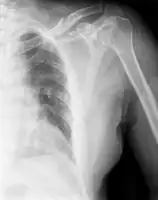

| X-ray of a left clavicle fracture | |

It is often caused by a fall onto a shoulder, outstretched arm, or direct trauma.[1][3] The fracture can also occur in a baby during childbirth.[1] The middle section of the clavicle is most often involved.[3] Diagnosis is typically based on symptoms and confirmed with X-rays.[2]

The basic method to check for a clavicle fracture is by an X-ray of the clavicle to determine the fracture type and extent of injury. In former times, X-rays were taken of both clavicle bones for comparison purposes. Due to the curved shape in a tilted plane X-rays are typically oriented with ~15° upwards facing tilt from the front. In more severe cases, a computerized tomography (CT) or magnetic resonance imaging (MRI) scan is taken. However, the standard method of diagnosis through ultrasound imaging performed in the emergency room may be equally accurate in children.[6]